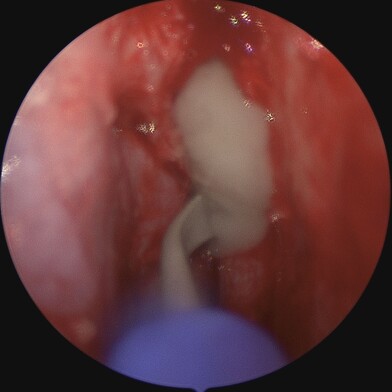

The endoscope is inserted through the nasal cavity to visualise and access the lacrimal sac and nasal bones. The bone is drilled away endoscopically, and a similar new pathway is created without external incisions. A mucosal flap is created to line the new passage connecting the lacrimal sac to the nasal cavity, ensuring proper drainage of tears. Silicone tubes or stents may be placed temporarily to keep the new pathway open and aid in healing.